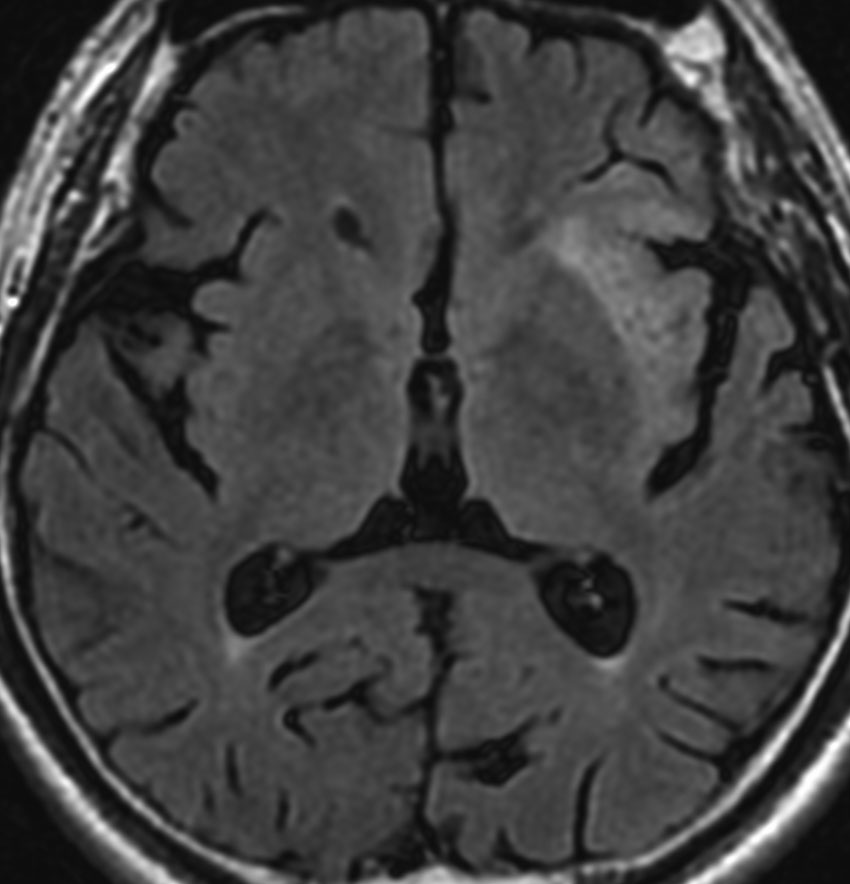

2010年無症状の時の画像です。こんなのを手術で摘出したら認知機能が落ちて人格が変わります。だから経過観察しました。

2015年のテモゾロマイドを開始する前の画像です。2014年にちょびっと生検術をして1p/19q欠失,IDH変異はわかっていました。2015年に全般発作を起こしたので治療を開始しました。テモゾロマイドを 2年 24コース続けました。乏突起膠腫は大きくなる時,てんかんを生じることが多いです。

2020年の画像です。腫瘍はかなり小さくなって再燃(再発)していません。てんかんも抑制されて発作はありません。無症状です。

この例は,手術も放射線治療もしないで,乏突起膠腫が10年以上,制御できることを示しています。また,テモゾロマイド治療でてんかん発作が少なくなることも有名な事実です。

でも,現実はこんなに甘くない?  2025年時点で,治癒を目指すなら低線量放射線治療を加えるべきと考えられています。